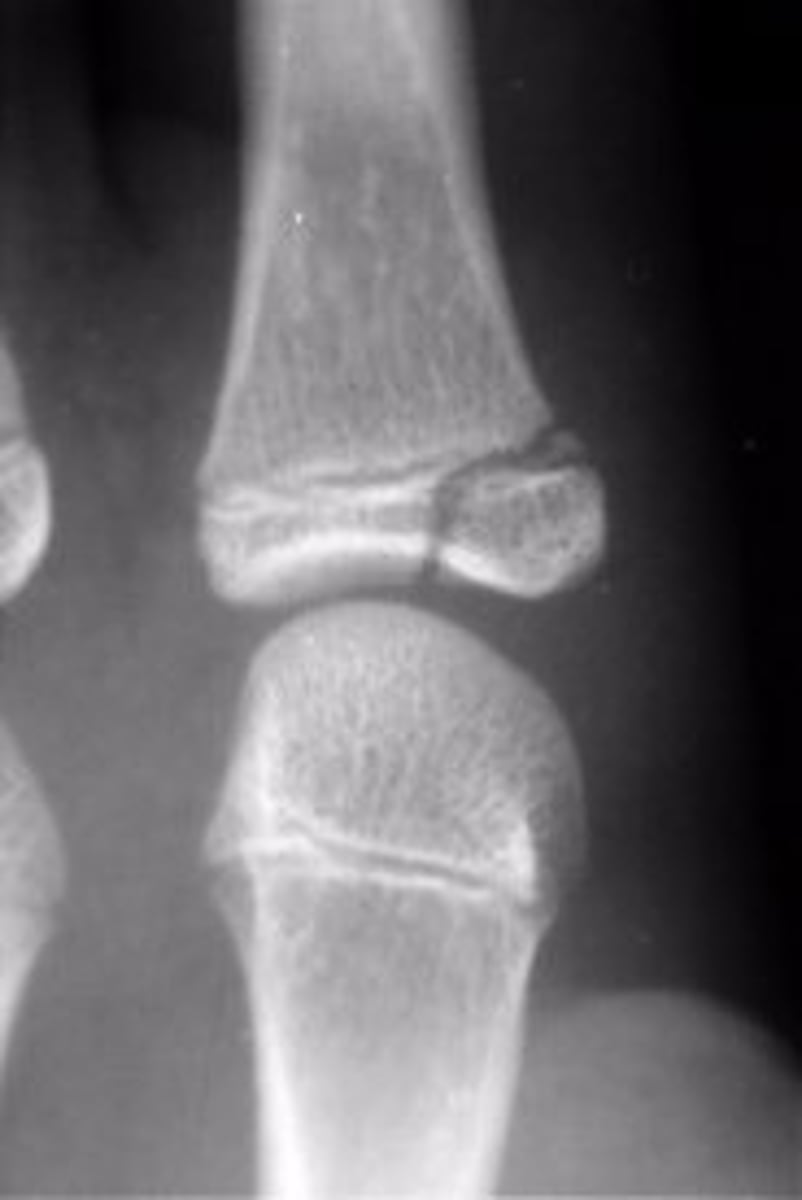

Salter Harris grade 1 growth plate fracture

Salter Harris grade?

Salter Harris grade 2 growth plate fracture

Salter Harris grade 3 growth plate fracture

Salter Harris grade 4 growth plate fracture

Salter Harris grade 5 growth plate fracture